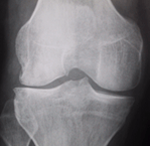

Le Diagnostic de l'arthrose repose sur la RADIO

L'arthrose s'apprécie sur une radio du genou, en position debout (en charge), les genoux légèrement pliés (en position de schuss). La radio permet de mesurer l'espace entre les deux os. Cet espace, l'interligne, correspond à l'épaisseur de cartilage.

Lorsque l'espace entre les deux os, l'interligne articulaire, est moins épais d'un côté du genou par rapport à l'autre, lorsqu'il est "pincé", on parle d'arthrose qui peut être débutante, modérée ou évoluée, en fonction de l'importance du pincement.

++++++++++++++Images radiologiques de l'arthrose

Au début, l'arthrose est le plus souvent partielle, "uni-compartimentale".

Arthrose fémoro-tibiale Interne

Arthrose débutante : petit pincement de l'interligne

Arthrose évoluée : pincement complet de l'interligne